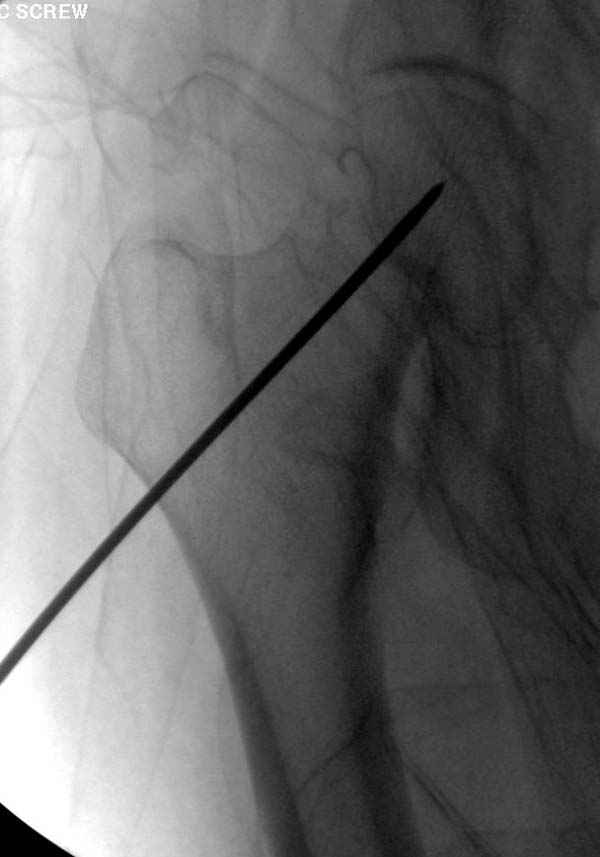

Профилактику дальнейшего раскола неполного перелома шейки провели тремя канюлированными шурупами.

в течение первых 72 часов после перелома, остеосинтез тремя спонгиозными шурупами.

Наверное речь идет насчет parallel guide из набора. Применяем по возможности всегда, но,

как видно на снимке, не всегда получается

паралельно.